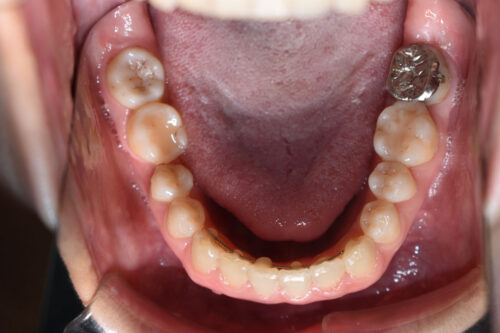

本症例も

下顎右側第一大臼歯欠損

上下とも歯が唇側に傾斜し

下の歯が上の歯よりも外にでている 受け口の状態でした。

ワイヤー8か月後です。